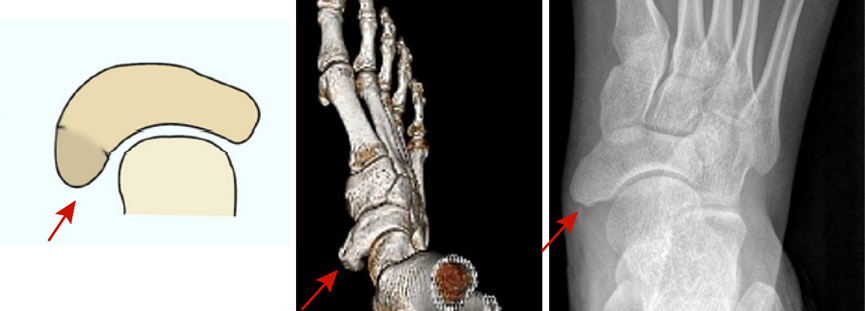

(二)足副舟骨的分型及意义

图4:Ⅱ型又称假关节型,此型最多见,约占50-60%。此型稳定性差,常因扭伤或劳累后诱发疼痛。

图5:Ⅲ型又称鸟嘴样或角形舟骨,约占4-21%,副舟骨与舟骨融合,关节面消失。此型结构较稳定,偶尔可出现疼痛性滑囊炎。